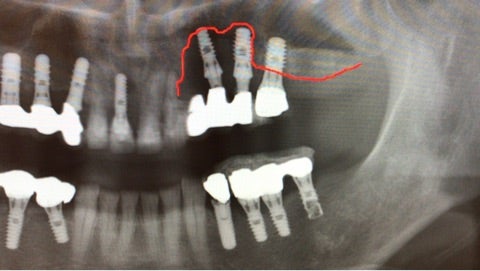

『昔通っていた歯科で埋入したインプラントの周りに違和感があり、最近になってグラグラしてきている』

▶︎赤いラインで引いた部分までインプラントの周りの骨が吸収していることがわかります。